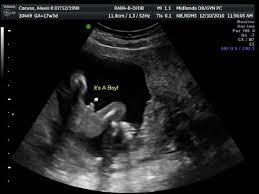

Mengalami masalah perkembangan baby 3. Meski air ketuban sering disebutkan selama kehamilan, masih ada bumil yang nggak banyak tahu tentang cairan volume air ketuban ini akan selalu dijaga dan dipertahankan kestabilannya di dalam tubuh. Apa jadi kalau air ketuban kurang? Cairan ketuban memang sangat bermanfaat bagi janin. Bacaan afi yang normal adalah antara 8 hingga 20, katanya kepada harian metro. Air ketuban banyak dalam istilah perubatan dipanggil sebagai polyhydroamnios. Bacaan air ketuban bacaan air ketuban klinik siti pristana facebook. Demikian juga bila kandung kemih ibu tertekan oleh rahim yang.